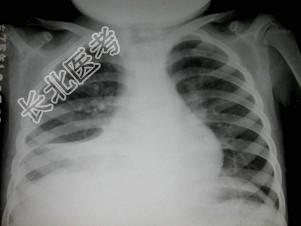

- 单项选择题女,6岁, 低热,盗汗, 咳痰,呼吸困难1月余, 结合图像,最可能的诊断是 ( )

A、肺脓肿

B、大叶性肺炎

C、右肺中叶综合征

D、肺癌

E、胸腔积液